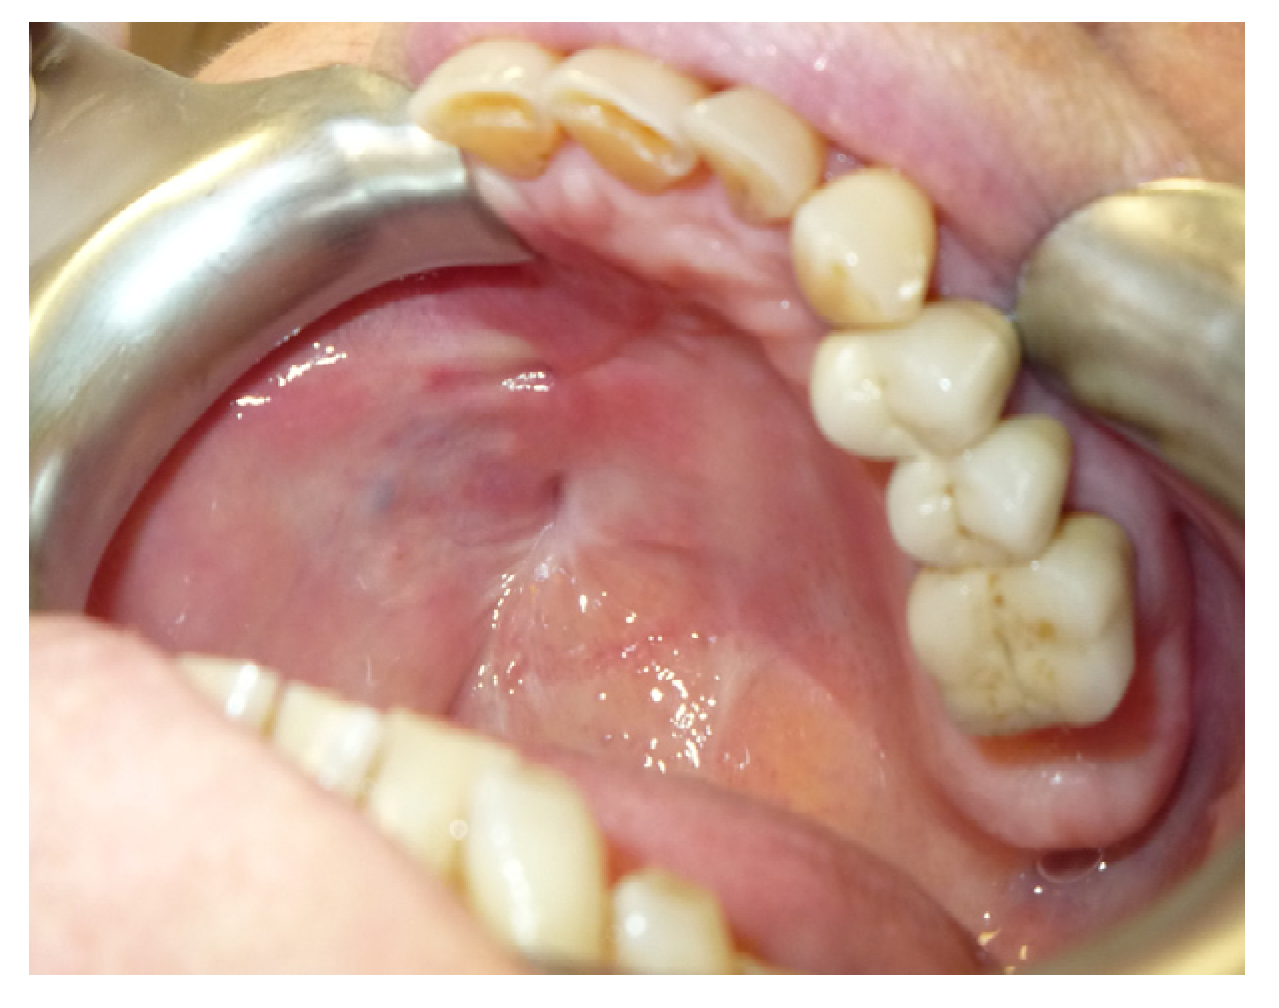

3.1.3. Case 3: R.M.

| R.M. | X | * | 9 | 0 | ||